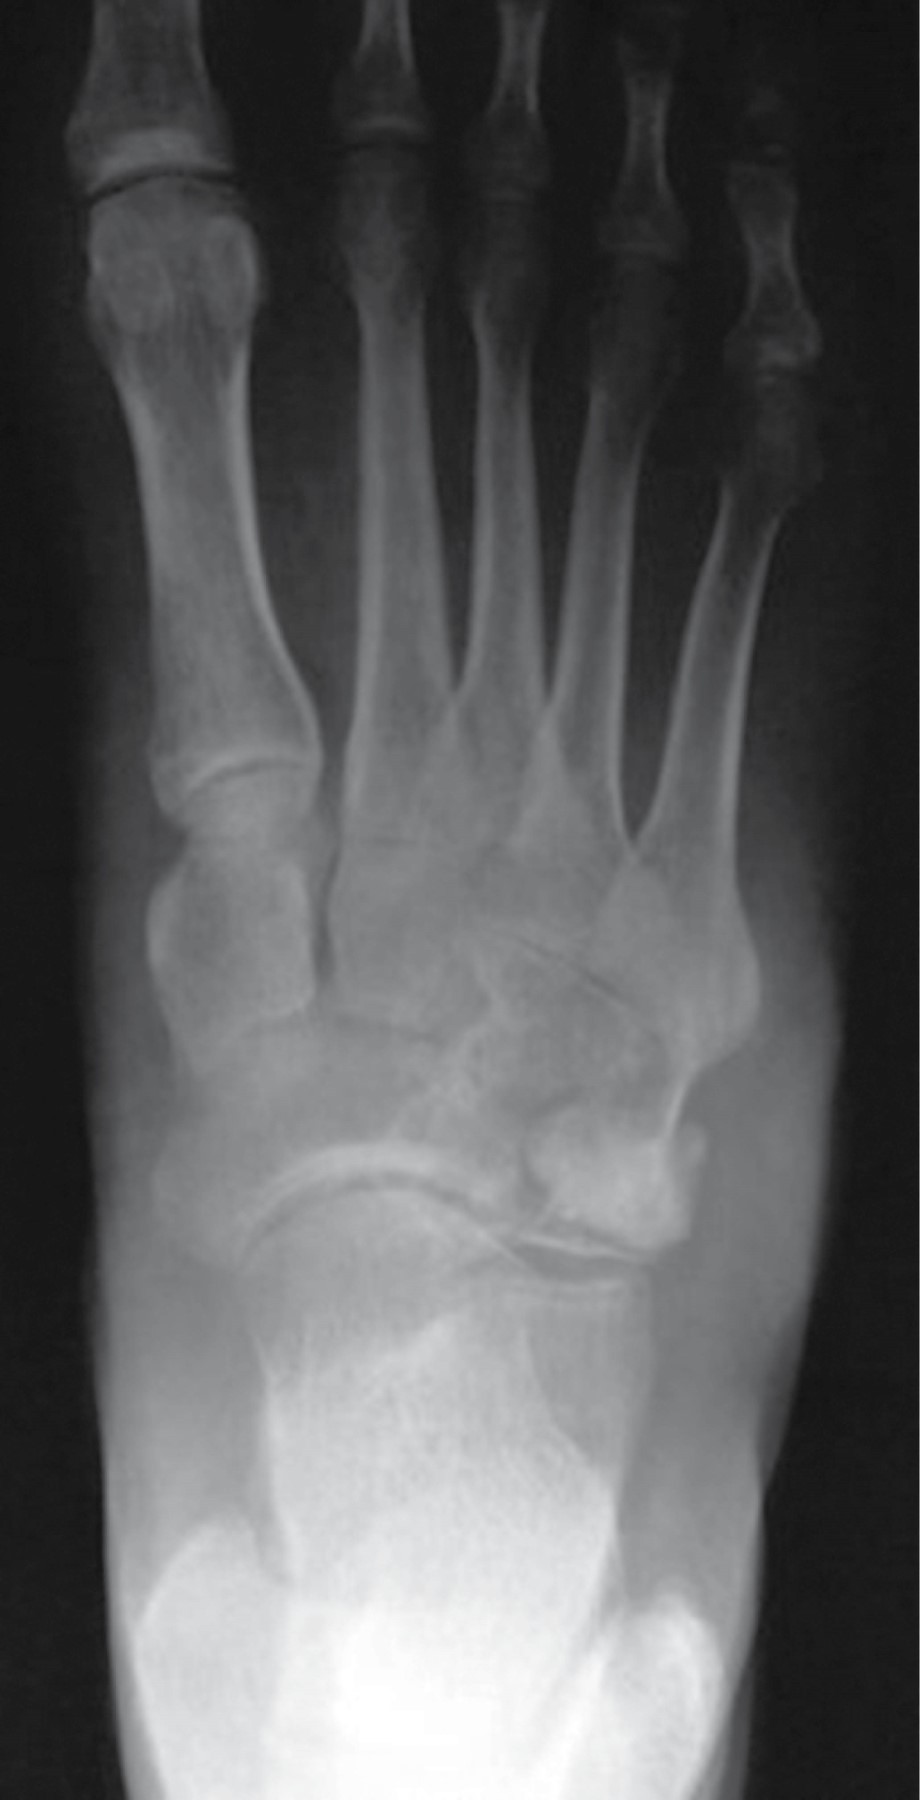

En las radiografías dorsoplantar y lateral de pie derecho se observa injerto óseo en el centro de una lesión en cuboides, radiotransparente, heterogénea, multilobulada, con bordes irregulares que sobrepasan la cortical lateral, multilobulados (Figuras 2 y 3).